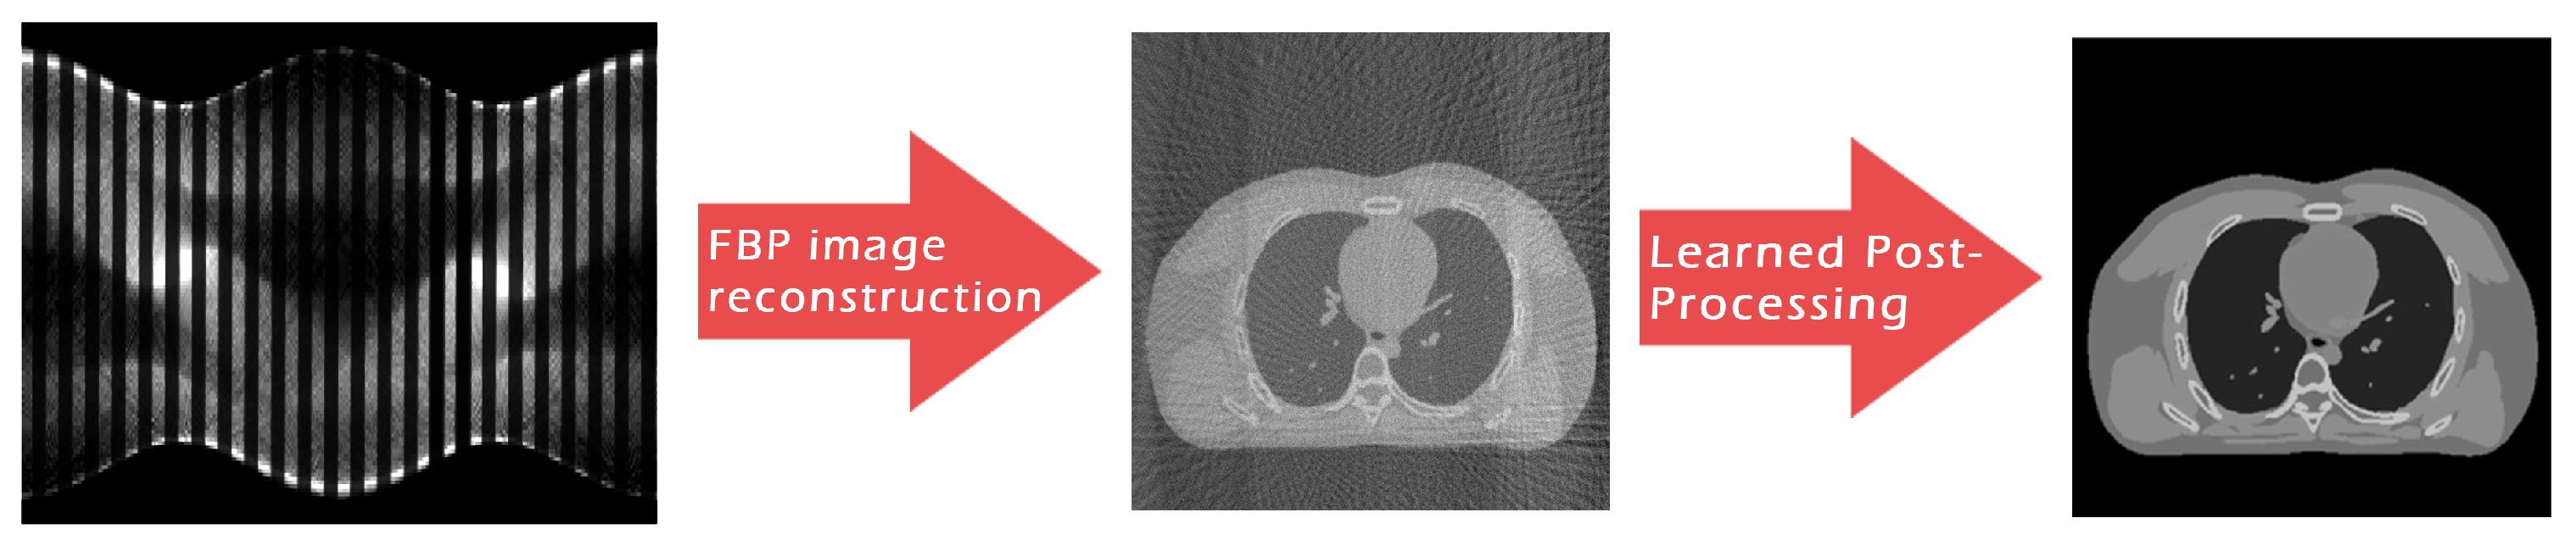

| FBP | 0.9966 | 86.42 (33.89) | 0.2924 | 0.5456 |

| ResUNet | 0.0942 | 106.99 (41.95) | 0.9262 | 0.9709 |

| 3L-SSNet | 0.0840 | 107.92 (42.32) | 0.9480 | 0.9627 |